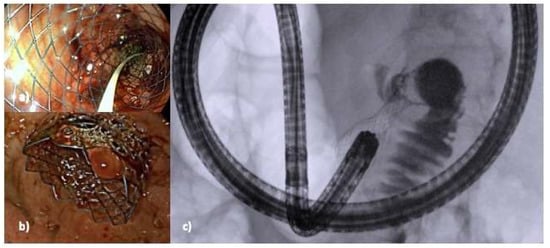

5.2. Device-Assisted EUS-GE

- Anderloni, A.; Fugazza, A.; Maia, L.; Auriemma, F.; Troncone, E.; Carrara, S.; Maselli, R.; Galtieri, P.; Semeraro, R.; Ferrara, E.; et al. Cautery-Tipped Lumen Apposing Metal Stent Placement Through the Mesh of an Indwelling Duodenal Self-Expanding Metal Stent. Am. J. Gastroenterol. 2018, 113, 644. [Google Scholar] [CrossRef]